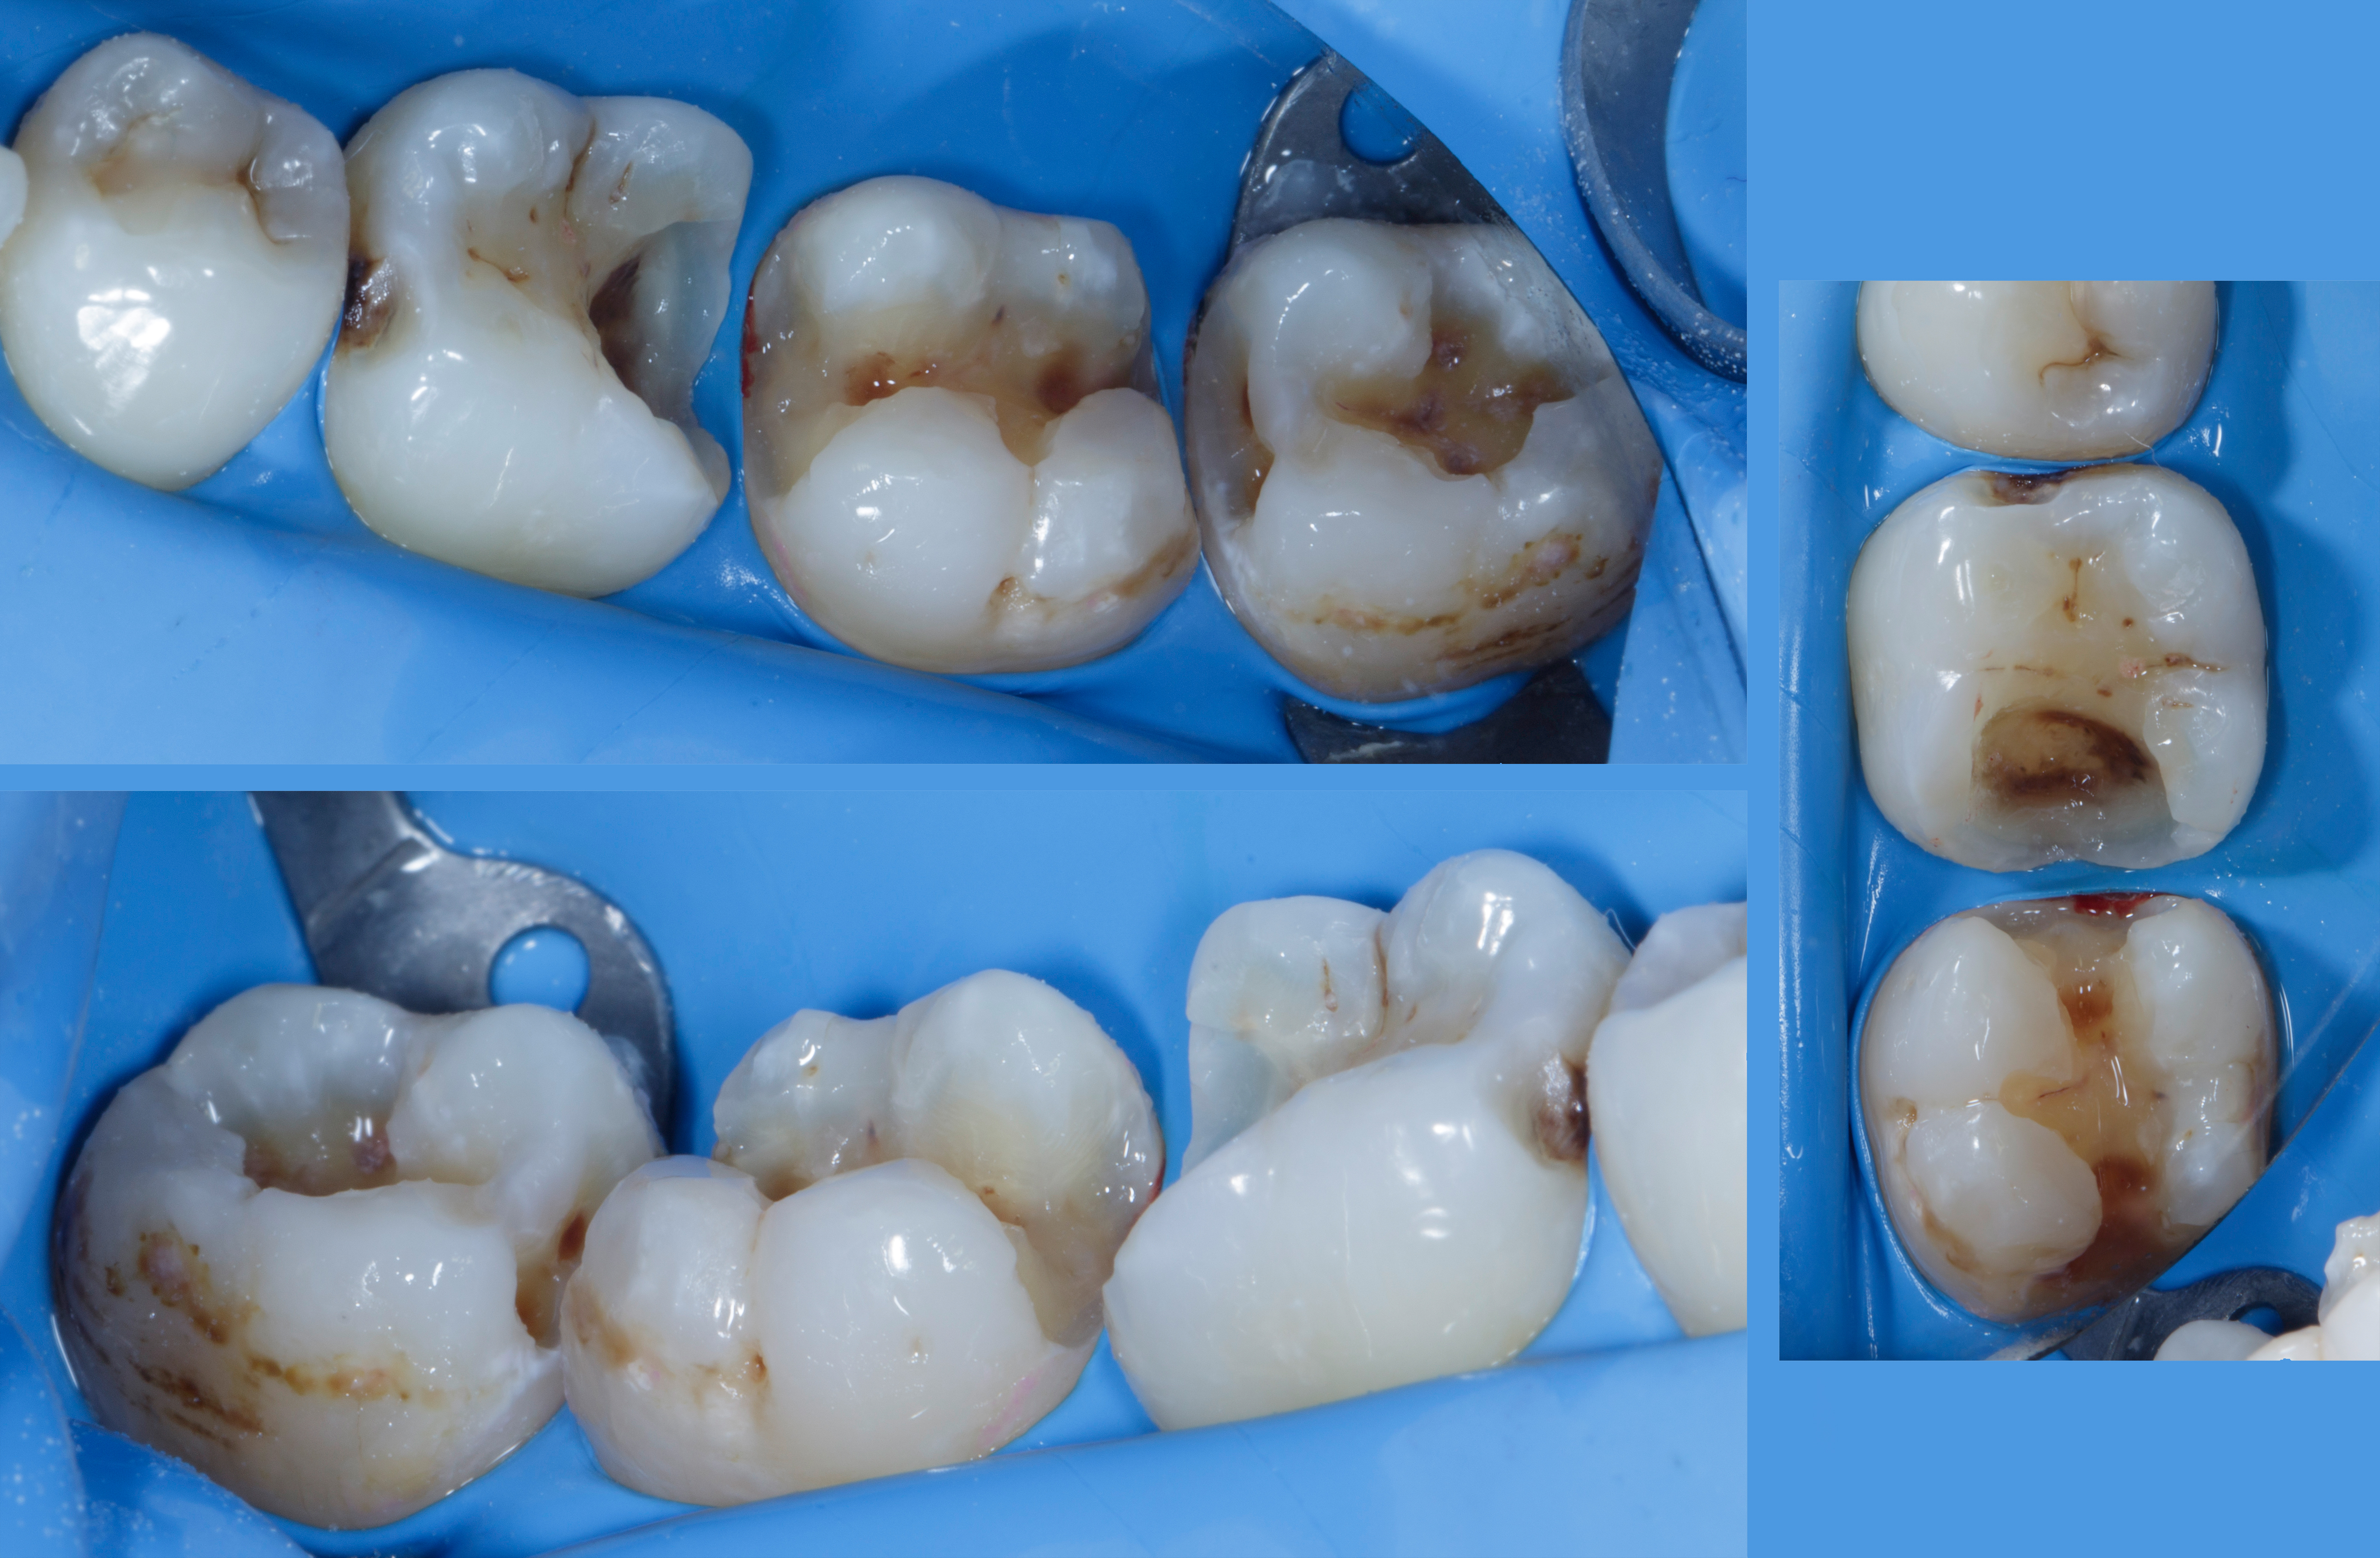

A 28-year-old woman presented to our office with complaints of sensitivity to cold temperatures and food impaction in her lower right quadrant. Her dental history revealed previous orthodontic treatment and multiple restoration failures in the same quadrant over the past 8-12 years.

Clinical examination showed significant mesio-occluso-distal (MOD) defects and Class 2 affecting teeth from #45 to #48.

Tooth #45: A distal carious lesion is suspected, potentially secondary to the adjacent mesial defect observed on tooth #46. No existing restoration is noted in this region, however, early discoloration and anatomical concavity suggest demineralization.

Tooth #46: Clinical examination revealed a mesial proximal carious defect with complete loss of the marginal ridge. On the distal aspect, an old composite restoration was observed, appearing underfilled and extended onto the occlusal surface. Evident marginal leakage and localized chipping were present along the restoration interface. Additionally, unsupported enamel was noted on the distobuccal cusp, indicating structural compromise and the risk of cusp fracture.

Tooth #47: An existing occlusal composite restoration demonstrated marginal discoloration and leakage. The distal surface exhibited a composite material of a different shade and texture, suggestive of a restoration placed at a later date. Lack of a defined marginal ridge resulted in an improper proximal contact. On the mesial surface, dark discoloration contiguous with the existing mesial pit composite indicated the presence of a recurrent or active Class II carious lesion.

Tooth #48: The mesial aspect showed dark discoloration extending into the existing mesial pit composite restoration, consistent with a developing or recurrent Class II carious lesion.

Bitewing radiograph confirmed the presence of multiple MOD / Class II carious lesions corresponding to the clinical findings. None of the defects demonstrated radiographic proximity to the pulp.

Figure 1. Multiple defects starting from tooth #45 to #48 as described above.Figure 2. Multiple class 2 defects starting from tooth #45 to #48 with loss of ideal contacts and contours.